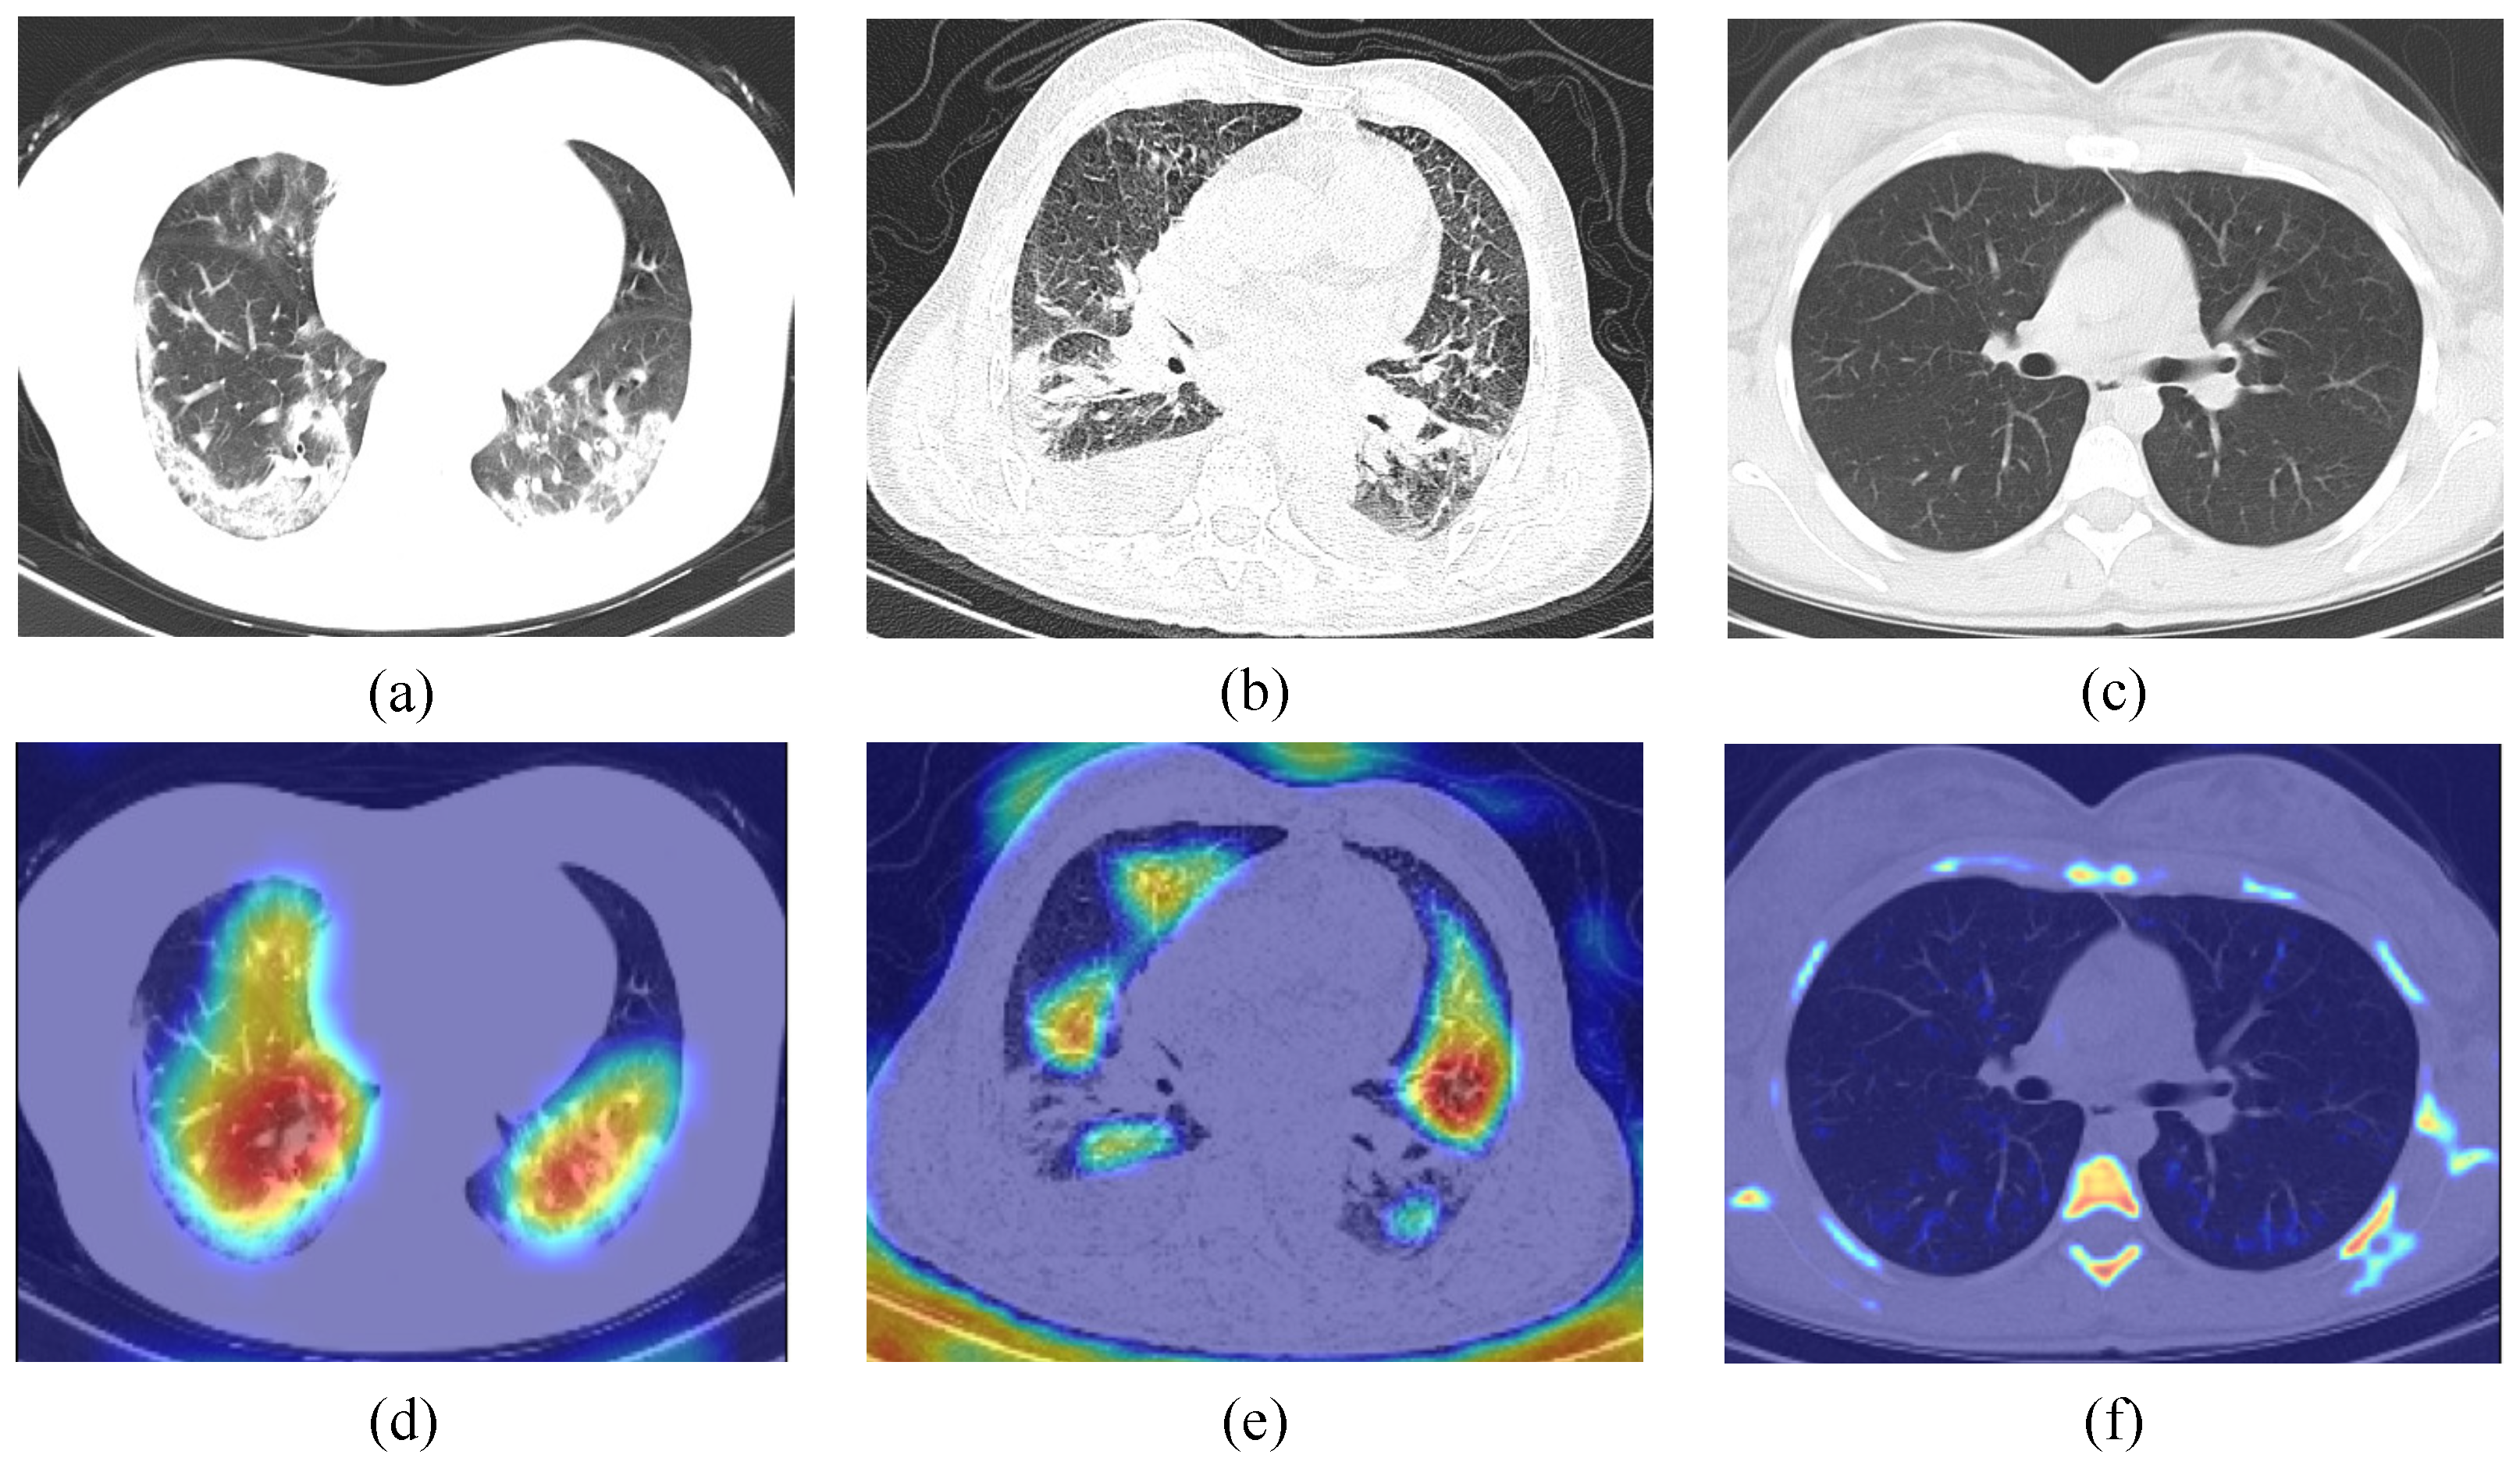

4.3.5. Lesion Visualization

To further illustrate the interpretability of the improved VGG19, the Grad-CAM [50] technique is used in this work. First, given an image and a target class as input, the feature map and the predicted values of the class are obtained by the CNN. Next, the predicted values of the target class are back-propagated to obtain the target class gradient information on the feature map, and then the feature map is a weighted summation and the heat map is obtained by ReLu. Finally, the heat map is upsampled to the resolution of the original map by bi-linear interpolation, and then superimposed with the original map to obtain the final visualization result. We randomly selected different categories of CT images (normal, pneumonia, and COVID-19) for validation. As shown in Figure 10, the CT images of COVID-19 and pneumonia have distinctive features, which are significantly different from the normal CT images; it demonstrates the applicability of our method in computer-aided medical diagnosis.

Figure 10.

Grad-CAM visualization. (a–c), respectively, represent COVID-19, pneumonia, and normal CT scan; (d–f), respectively, represent heatmap of (a–c).